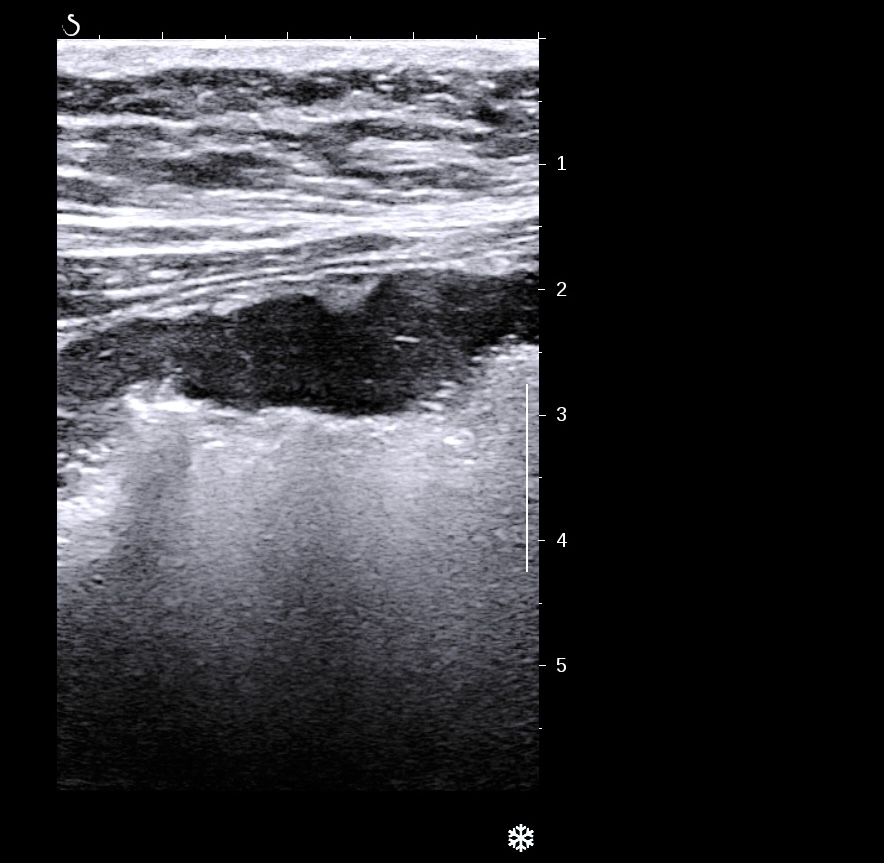

Forme plus chronique, épaississement très important de la sous muqueuse hyperéchogène par rapport à la muqueuse elle fait plus > 3/4 de la paroi

Forme chronique, aspect tubulisé du côlon, qui devient linéaire et rigide

Le doppler est souvent limité à la paroi (Limberg 1 et 2), la graisse peu ou pas infiltrée